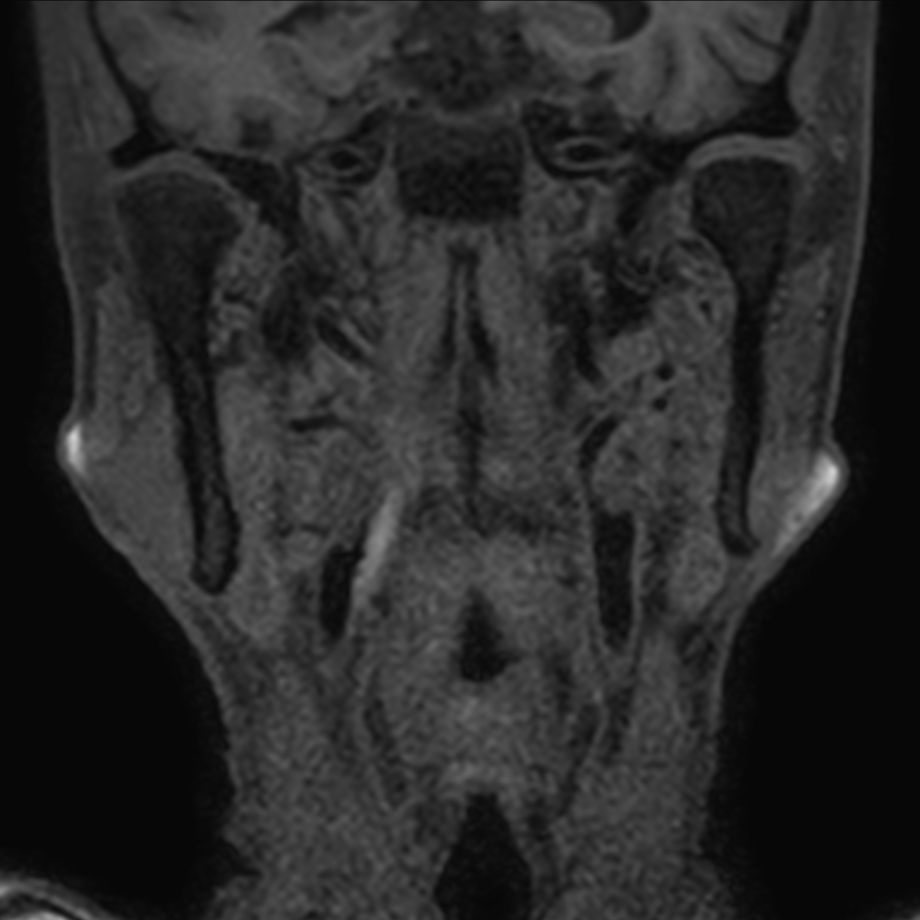

Patient with a neck stenosis. Compressed SENSE is used to shorten the total exam time.

3D T1w TSE Black Blood - Compressed SENSE